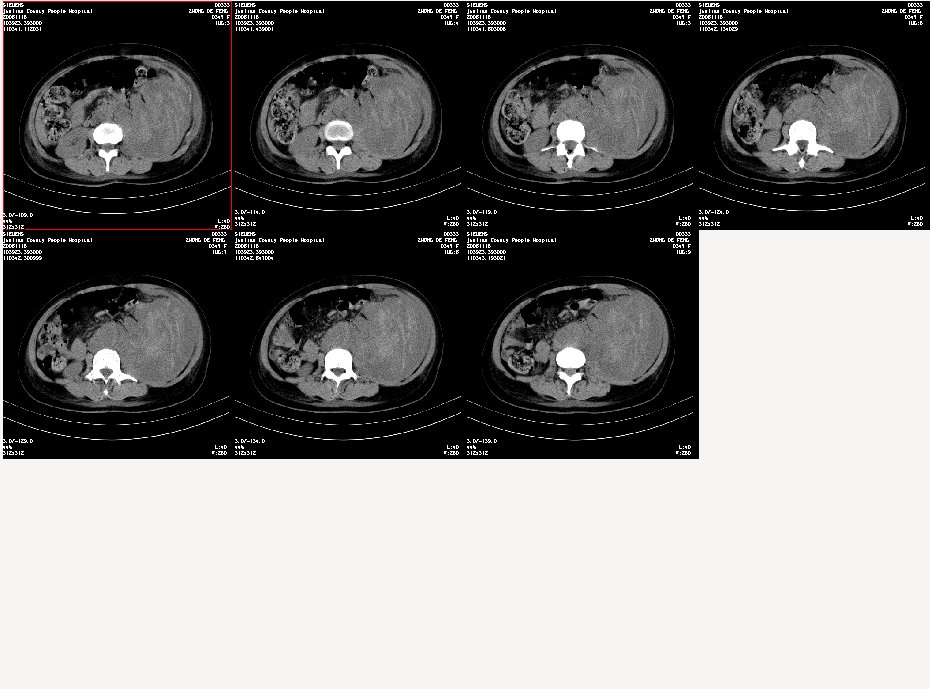

女,34岁,发觉腹部包块1周,查体:腹膨隆,左腹自肋下至髂嵴扪及10x8cm左右包块,触痛明显,固定

肿块来源不好确定,多种可能,来源于肾脏(肾癌),腹膜后(淋巴瘤)。小肠(肉瘤)。一切可能皆有,强化后再说

定位:腹膜后。来源:资料不完整,看不出来。定性:恶性。

病变自脾下至盆腔,范围广泛,左肾显示不清,似向前内侧推移,考虑病变来源于腹膜后;病变边界不清恶性可能性大;建议增强进一步明确。

到三级医院增强结果出来了,是腹主动脉瘤破裂出血,血肿形成。